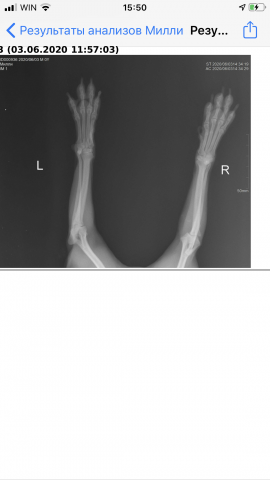

Добрый день! Помогите пожалуйста, вчера произошла ужасная ситуация. У меня Йорк, Милли. 5 лет 7 месяцев, вес 2500 кг. Вчера войдя домой, закрывала дверь и она решила проскочить на улицу и тут ее ударила дверь, по правой лапке(((((

Сразу поехала в ветеринарную клинику, сделали снимок. Сказали три пальчика перелом. Шок!!((((( вот хотела бы спросить, я вышлю снимок, что Делать в такой ситуации. В двух ветеринарных клиниках говорят разные мнения.